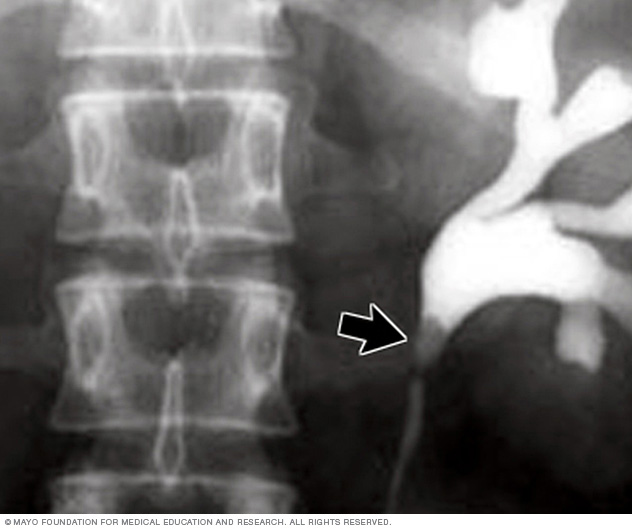

X-ray image of kidney stone

This X-ray using contrast reveals a kidney stone at the junction of the kidney and the tube that connects the kidney to the bladder, called the ureter.